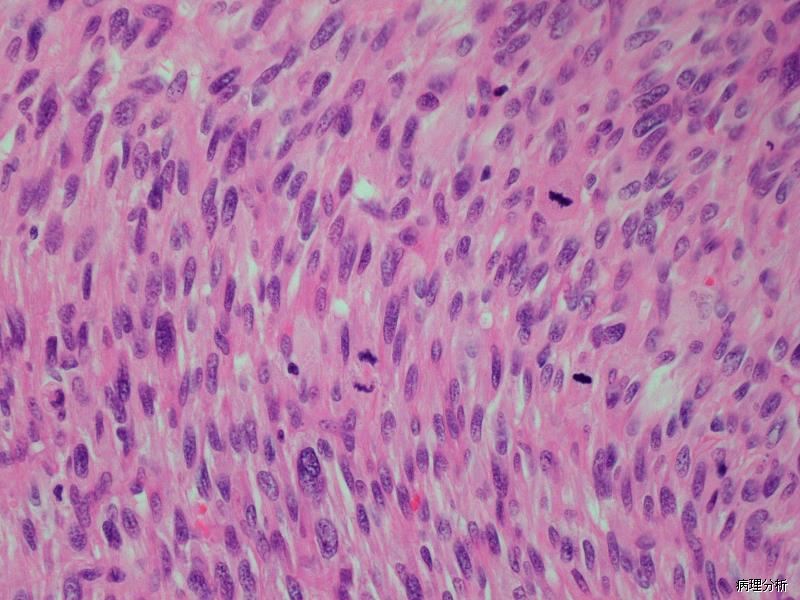

子宫梭形细胞平滑肌肉瘤

Spindle Cell Leiomyosarcoma of the Uterine

恶性平滑肌肿瘤,表现为梭形细胞形态。

梭形平滑肌样细胞密集增生,呈束状、编织状或杂乱排列;

细胞中-重度核异型,细胞核呈梭形,通常末端钝圆,核深染,染色质粗,核仁明显,50%的病例可见多核细胞和破骨样细胞;少数病例细胞仅轻度异型;

核分裂指数常很高(>10 个/10 个 HPF);